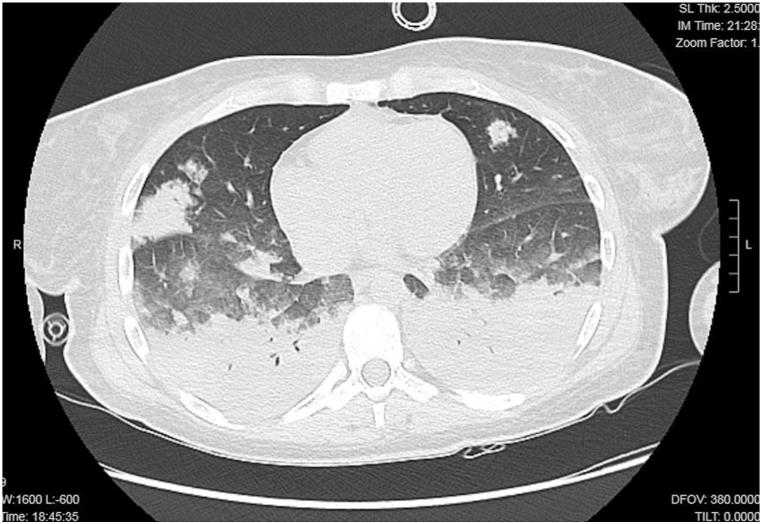

We report the case of a 34-year-old previously healthy female who developed acute respiratory failure after completing a prophylactic regimen of mefloquine for malaria prevention. The patient initially presented with fever, dyspnea, and hypoxemia, rapidly progressing to severe respiratory distress requiring invasive mechanical ventilation. Laboratory tests revealed marked eosinophilia, while thoracic computed tomography (CT) demonstrated diffuse ground-glass opacities and nodular infiltrates. Bronchoalveolar lavage (BAL) was positive for Rhinovirus, suggesting a possible interplay between drug-induced hypersensitivity and viral infection. Following corticosteroid therapy and supportive care, the patient's condition improved, with resolution of eosinophilia and radiological abnormalities.

我们报告一例34岁既往健康的女性,在完成预防疟疾的甲氟喹预防方案后发生急性呼吸衰竭。患者最初表现为发热、呼吸困难和低氧血症,迅速进展为严重呼吸窘迫,需要有创机械通气。实验室检查显示明显的嗜酸性粒细胞增多,而胸部计算机断层扫描(CT)显示弥漫性磨玻璃影和结节状浸润。支气管肺泡灌洗(BAL)检测出鼻病毒阳性,提示药物性超敏反应与病毒感染之间可能存在相互作用。经过糖皮质激素治疗和支持治疗,患者病情改善,嗜酸性粒细胞增多和影像学异常消失。